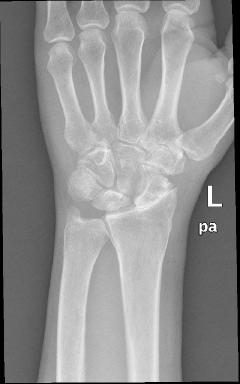

Kαρπός - Ασθενής 1 - Προεγχειρητικά